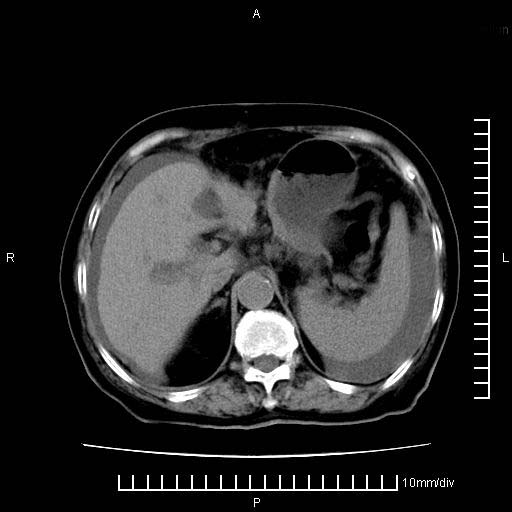

胰腺体部癌累及周围器官,腹膜、粘连

1。胰腺ca伴腹膜腔转移

胰腺结构模糊,胰尾部见囊性包块,周围脂肪密度增高,左肾前筋膜增厚,胸水、腹水。不符合胰腺ca伴腹膜腔转移。考虑胰腺炎伴假性囊肿形成、胸腹腔积液。

1)考虑胰腺癌并胰腺假性囊肿形成。2)肝内低密度灶,不排除转移。3)右肾盂积水。4)腹水。5)右侧胸腔积液并右肺下叶部分膨胀不全。